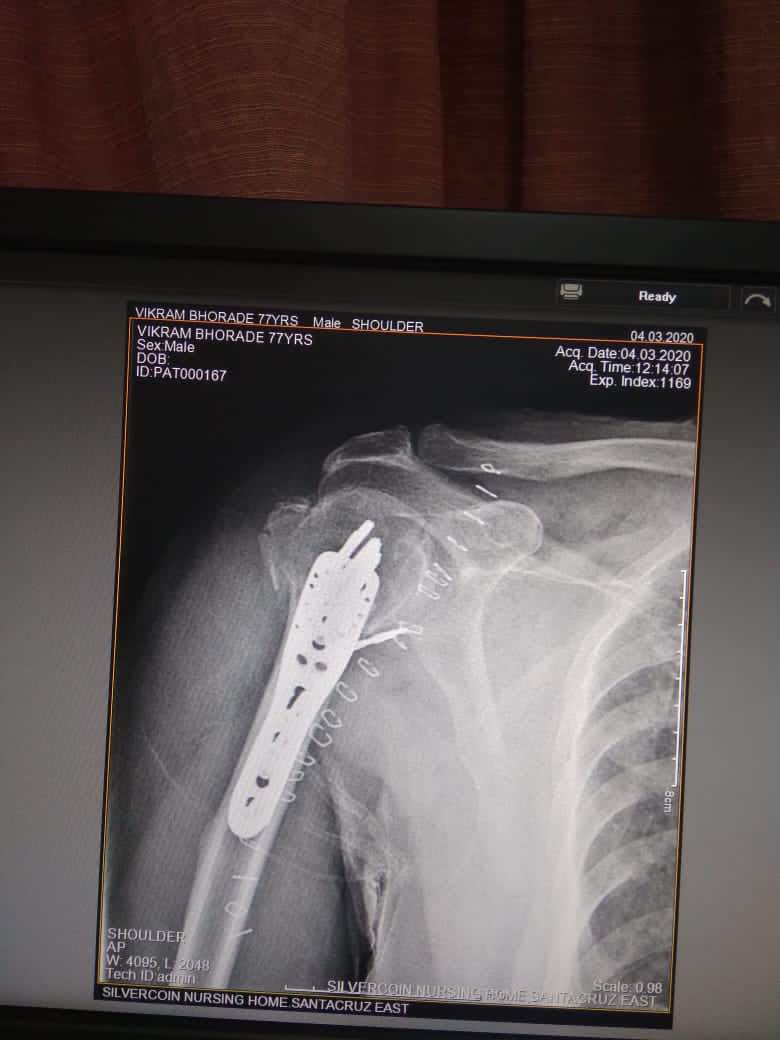

Beat SHOULDER SURGEON IN Andheri